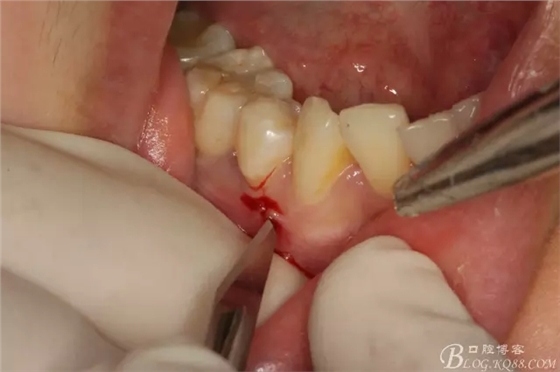

圖5.局部麻醉下、在44近中做垂直小切口,切口不要超過(guò)膜齦聯(lián)合。

圖6.齦溝內(nèi)水平切口

圖7.翻小瓣。暴露45牙根斷面